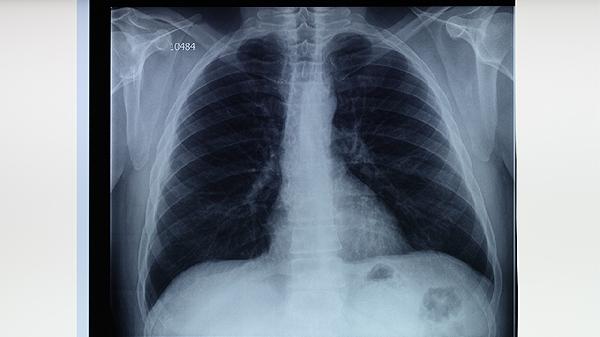

患者需單獨使用餐具并定期煮沸消毒,房間每日通風30分鐘。注意監(jiān)測體溫和體重變化,記錄咳嗽、咯血等癥狀。治療期間避免去人群密集場所,外出佩戴口罩。保證每日8小時睡眠,可進行呼吸操等輕度運動。每月復查胸部X線或CT,持續(xù)用藥至少6-9個月直至醫(yī)生確認痊愈。